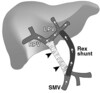

rex shunt

A derivação meso-porta, também conhecida como shunt Rex, é uma cirurgia que envolve a colocação de um enxerto de veia jugular entre a veia mesentérica superior e o ramo esquerdo intra-hepático da veia porta. Essa técnica é utilizada para tratar a obstrução extra-hepática da veia porta (OEHVP), que pode causar hipertensão portal e varizes esofágicas. A cirurgia restaura o fluxo sanguíneo venoso esplâncnico para o fígado, normalizando a fisiologia hepato-intestinal e reduzindo a pressão portal, o que pode levar à recuperação de sintomas como esplenomegalia e varizes.